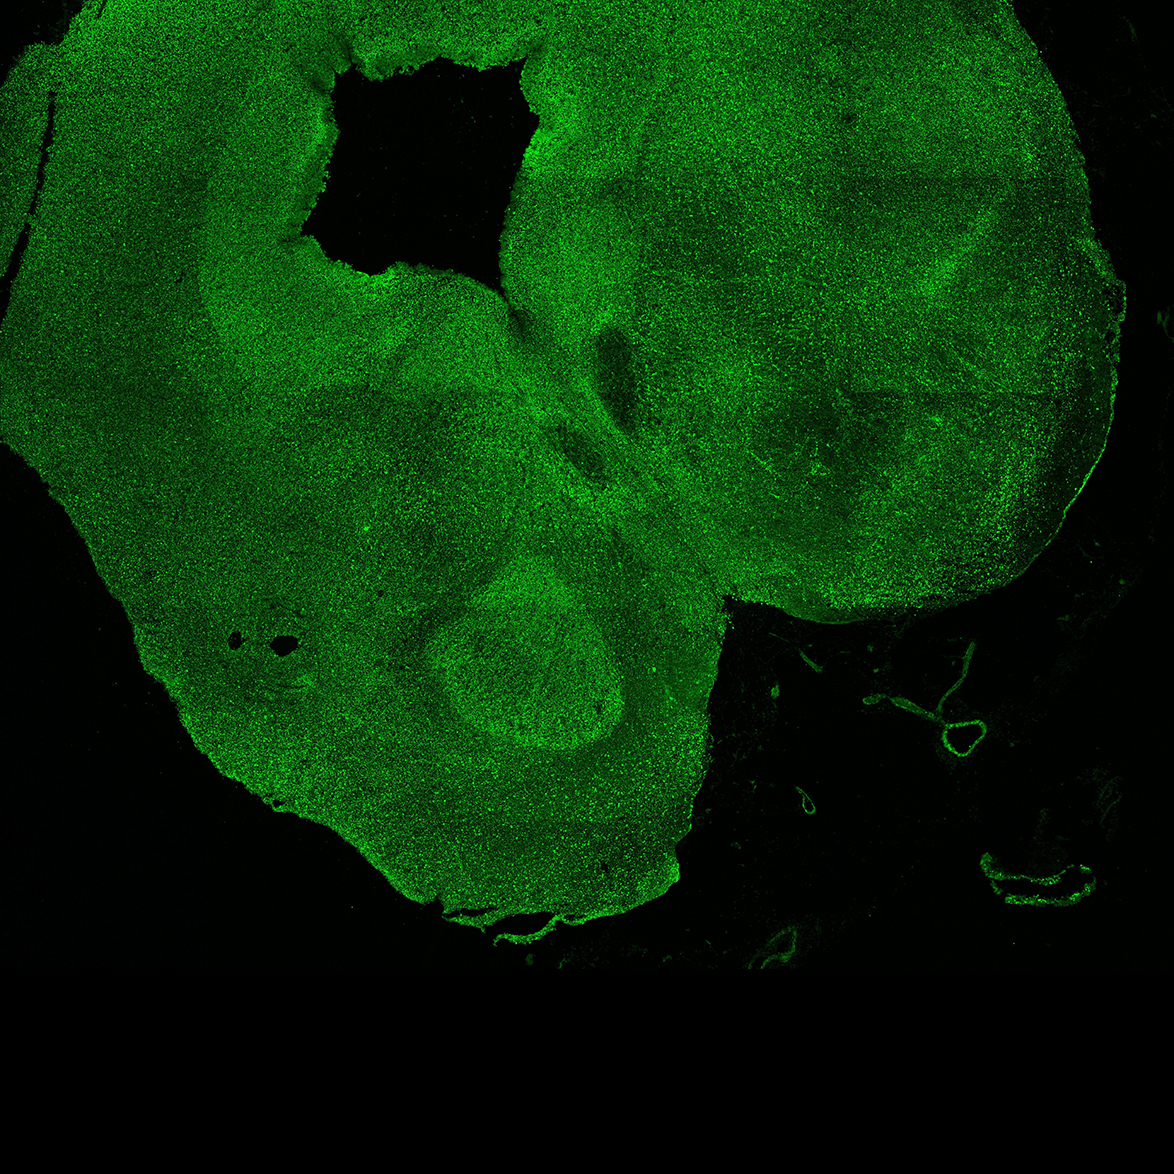

An anatomical analysis of the developing human midbrain from 6 post-conceptional weeks (PCW) to 22 PCW reveals increased tissue complexity, characterized by the emergence of dopaminergic nuclei, as highlighted by immunofluorescence analysis for tyrosine hydroxylase (TH).

DAPI

22PCW human midbrain

GFAP

TH

Merged